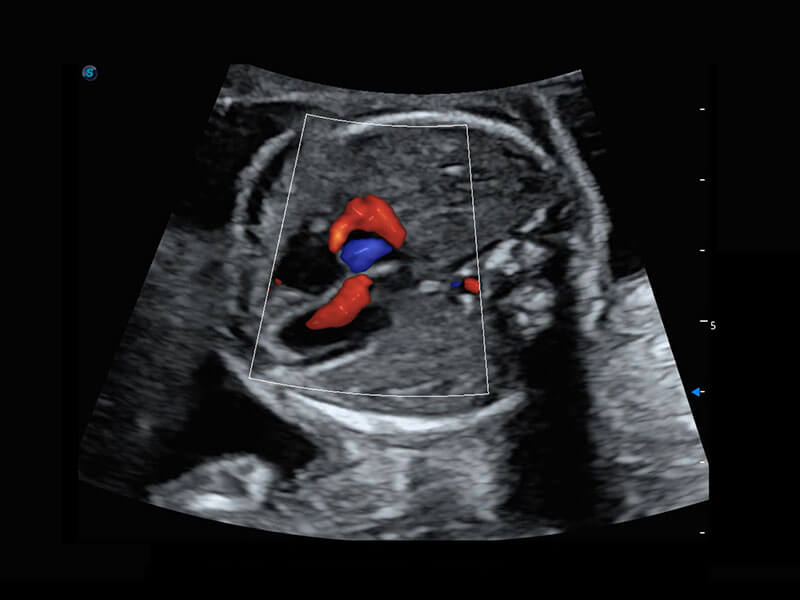

四腔心血流

P60搭载一系列胎儿心脏成像技术,实现精细的胎儿心脏评估。